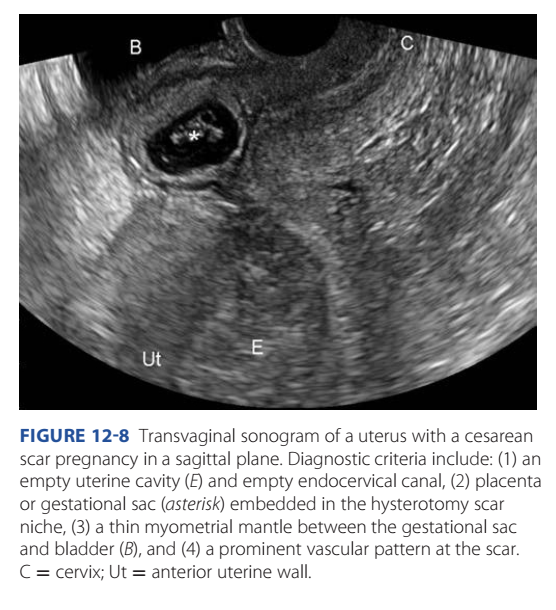

Sonographic criteria are described in Figure 12-8 (imor-

FiGURE 12-8 Transvaginal sonogram of a uterus with a cesarean

scar pregnancy in a sagittal plane. Diagnostic criteria include: (1) an

empty uterine cavity (E) and empty endocervical canal, (2) placenta

or gestational sac (asterisk) embedded in the hysterotomy scar

niche, (3) a thin myometrial mantle between the gestational sac

and bladder (B), and (4) a prominent vascular pattern at the scar.

C = cervix; Ut = anterior uterine wall.230 First- and Second-Trimester Pregnancy Loss